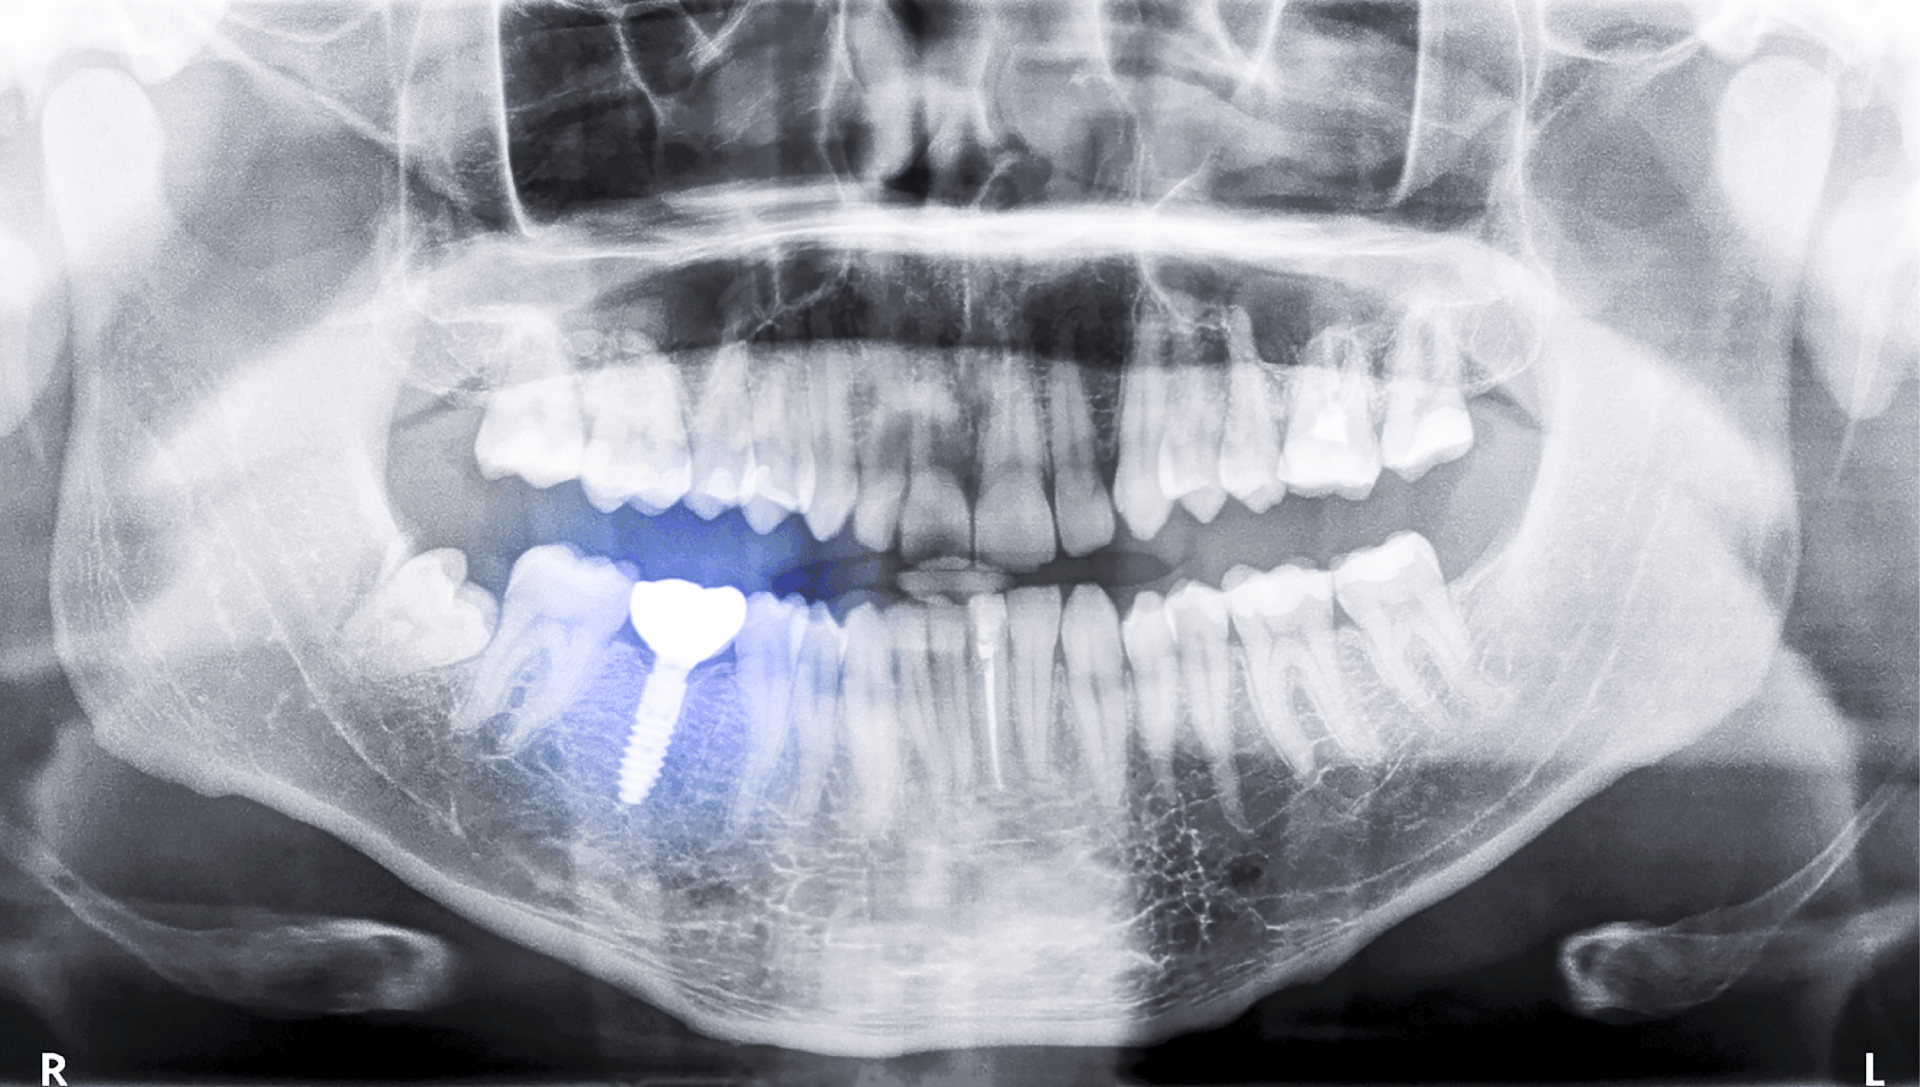

Prima di procedere con l’intervento, la prima cosa da fare è un’analisi completa delle situazioni organiche generali e specifiche della zona da trattare. Tra di esse si ricercano: patologie in atto o passate, l’assunzione di farmaci, la presenza di malattie croniche come il diabete e l’ipertensione. La situazione organica locale si valuta con l’esame obiettivo, le radiografie, i calchi in gesso, le fotografie e, se è il caso con la CBCT (TAC).

In base alle risultanze dello studio della situazione, si decide il tipo di impianto e di dente da realizzare.